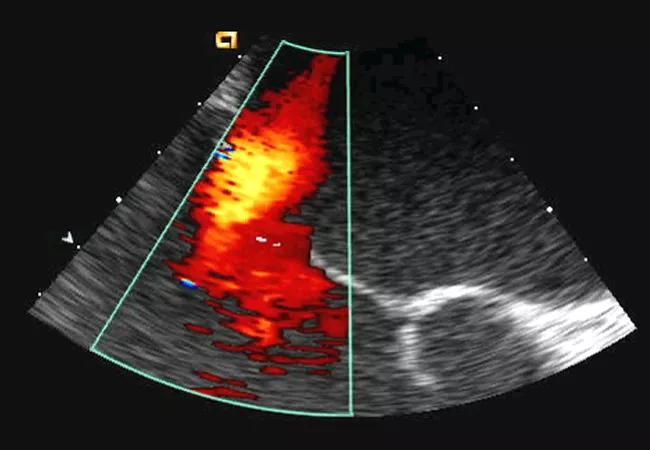

Figure 1. Representative echo (not from the case patient) showing anterior leaflet mitral valve prolapse and posterior-directed mitral regurgitation jet.

Mitral valve prolapse